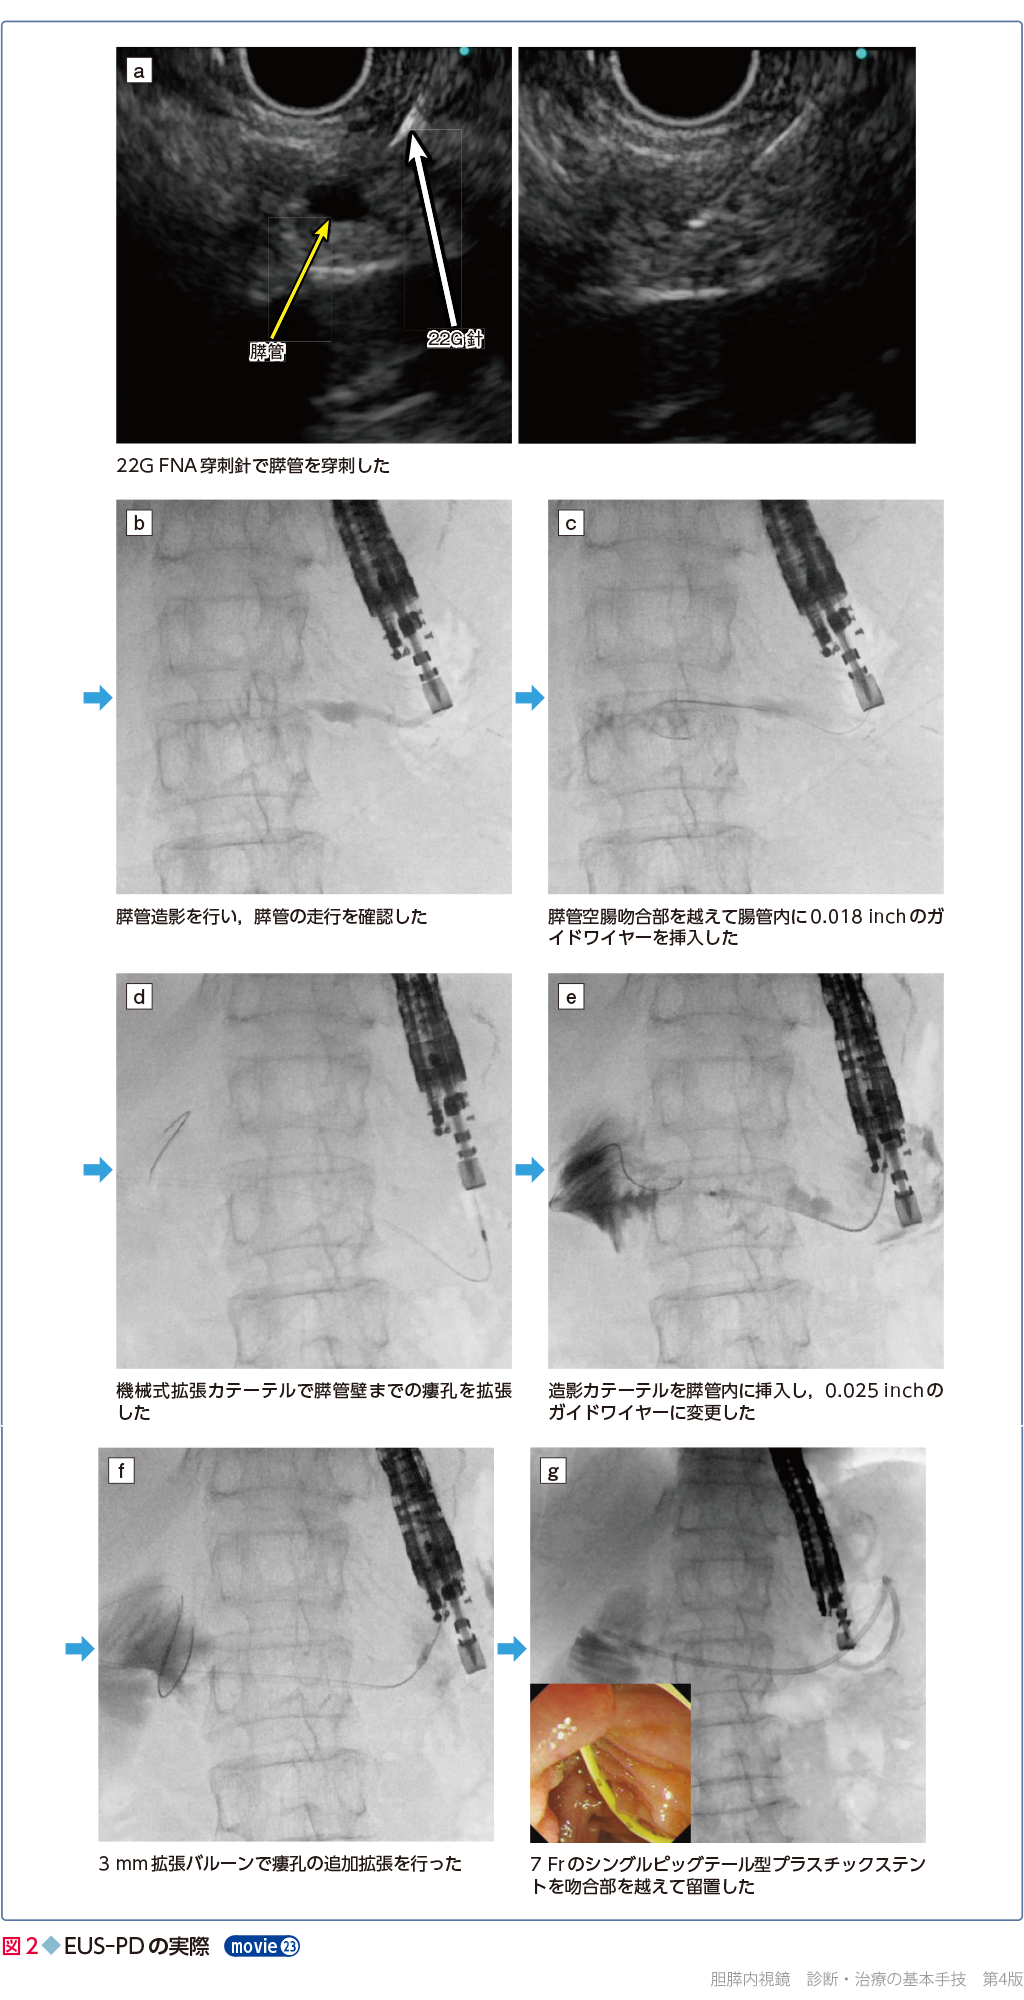

胆膵内視鏡の診断・治療の基本手技 第3版 | 糸井 隆夫 |本。胆膵内視鏡 診断・治療の基本手技 第4版 | 糸井 隆夫 |本 | 通販。胆膵内視鏡の診断・治療の基本手技 第3版 | 糸井 隆夫 |本。国産米粉のホットケーキミックス☆驚くほどもっちり☆MOLINAGA☆2袋セット。胆膵内視鏡 診断・治療の基本手技 第4版 - 羊土社。最先端治療 胆道がん・膵臓がん – 法研。裁断済(バラバラ)の本です。胆膵内視鏡の診断・治療の基本手技 第3版 - 羊土社。。胆膵内視鏡 診断・治療の基本手技 第4版 - 羊土社。胆膵内視鏡でサポートバンドを導入 - 事例紹介|Medicle。内視鏡センター|社会医療法人三栄会 ツカザキ病院。胆膵内視鏡の診断・治療の基本手技 改訂2版」付録DVD。胆膵内視鏡の診断・治療の基本手技 - 羊土社。裁断済みの為、状態が悪いとしていますが、書き込み等ございません。使い方の分かる方のご購入をお願いいたします。JDDWで売上1位を獲得した話題の新刊『これで完璧!胆膵内視鏡の